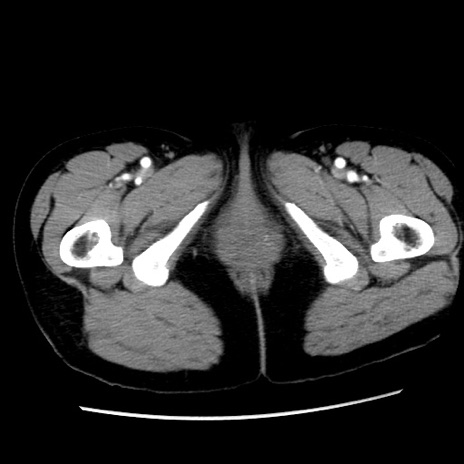

症例10(横断像)

【症例】 50歳代女性

【主訴】 腹痛

【現病歴】前日生レバーを食べた。今朝に排便あり。 昼前に突然発症の腹痛を生じ、当院救急外来を受診した。

【既往歴】 子宮筋腫にてで子宮全摘後

【身体所見】 意識清明、腹部:平坦、軟、下腹部やや左を中心に圧痛・反跳痛あり、筋性防御あり

【データ】WBC 7800、CRP 0.07